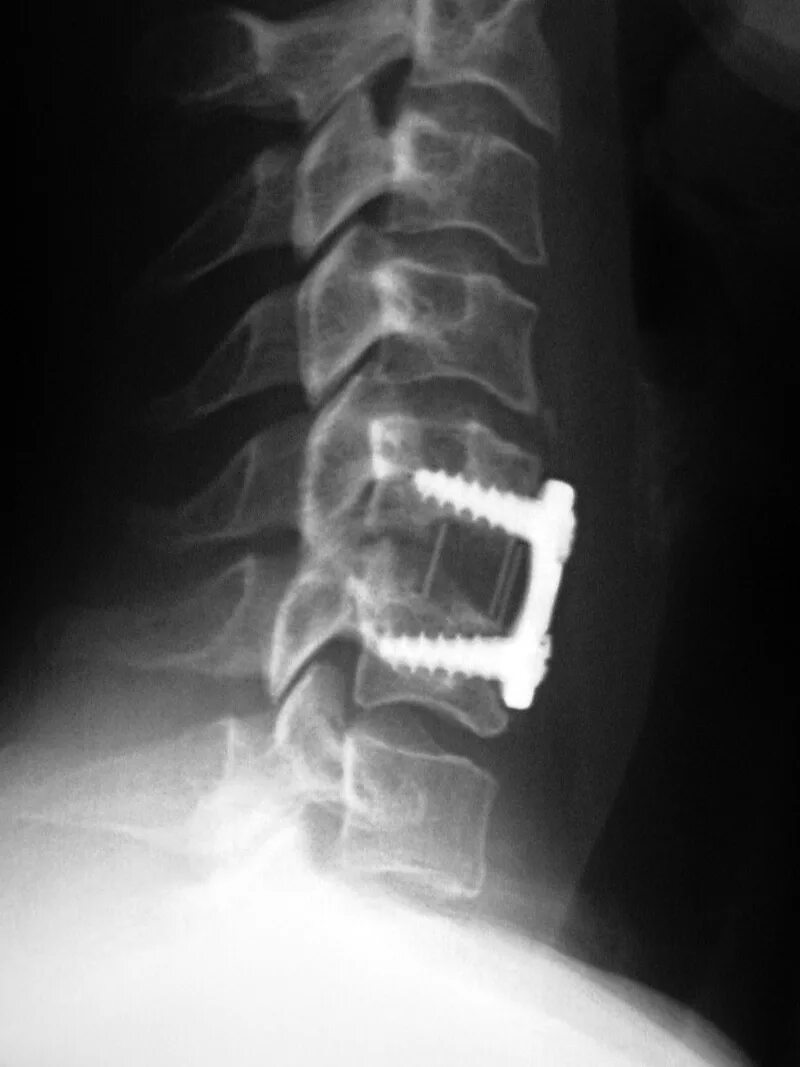

Установка кейджа в позвоночнике